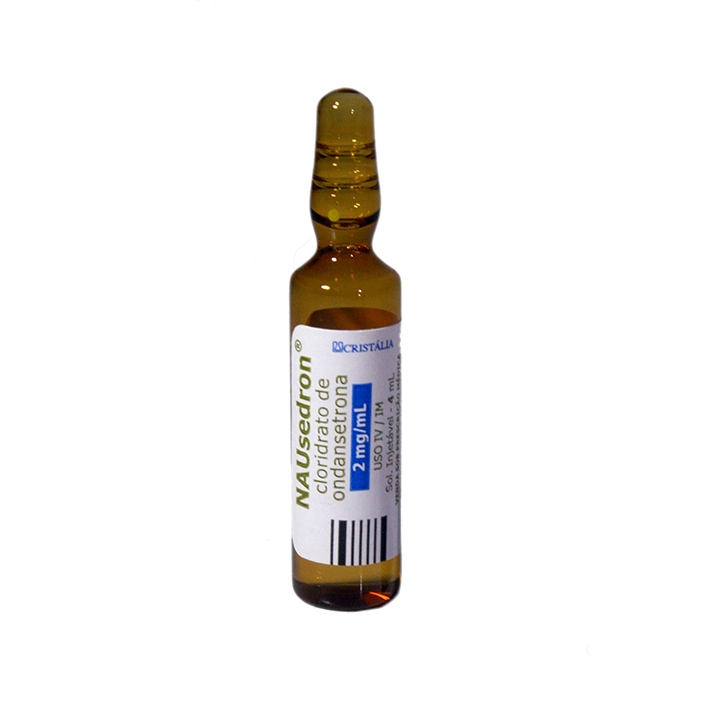

Ondansetrona e o risco de morte súbita em hemodiálise

Ondansetrona e o risco de morte súbita em hemodiálise

Como assim risco de morte súbita com Ondansetrona? Atenção especial aos pacientes com polifarmácia e risco de QT longo!